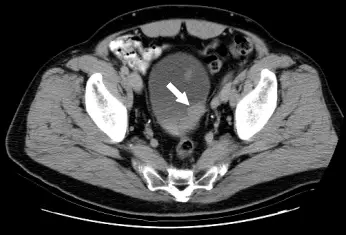

46 歲林先生因排解血尿而到醫院檢查,他並沒有其他不舒適症狀。醫師為他做 IVU 檢查顯示膀胱異常,又進一步做 CT 檢查,病變如圖示。林先生最可能患了什麼病? 圖片 圖片 圖片

圖二(CT 軸位切面,上方切面):骨盆 CT 橫斷面影像顯示充盈的膀胱,白色箭頭指向膀胱後壁的局部壁增厚(focal wall thickening)或腔內腫塊,呈現軟組織密度,強化後與膀胱壁連接,提示為膀胱壁來源的腫瘤性病灶。